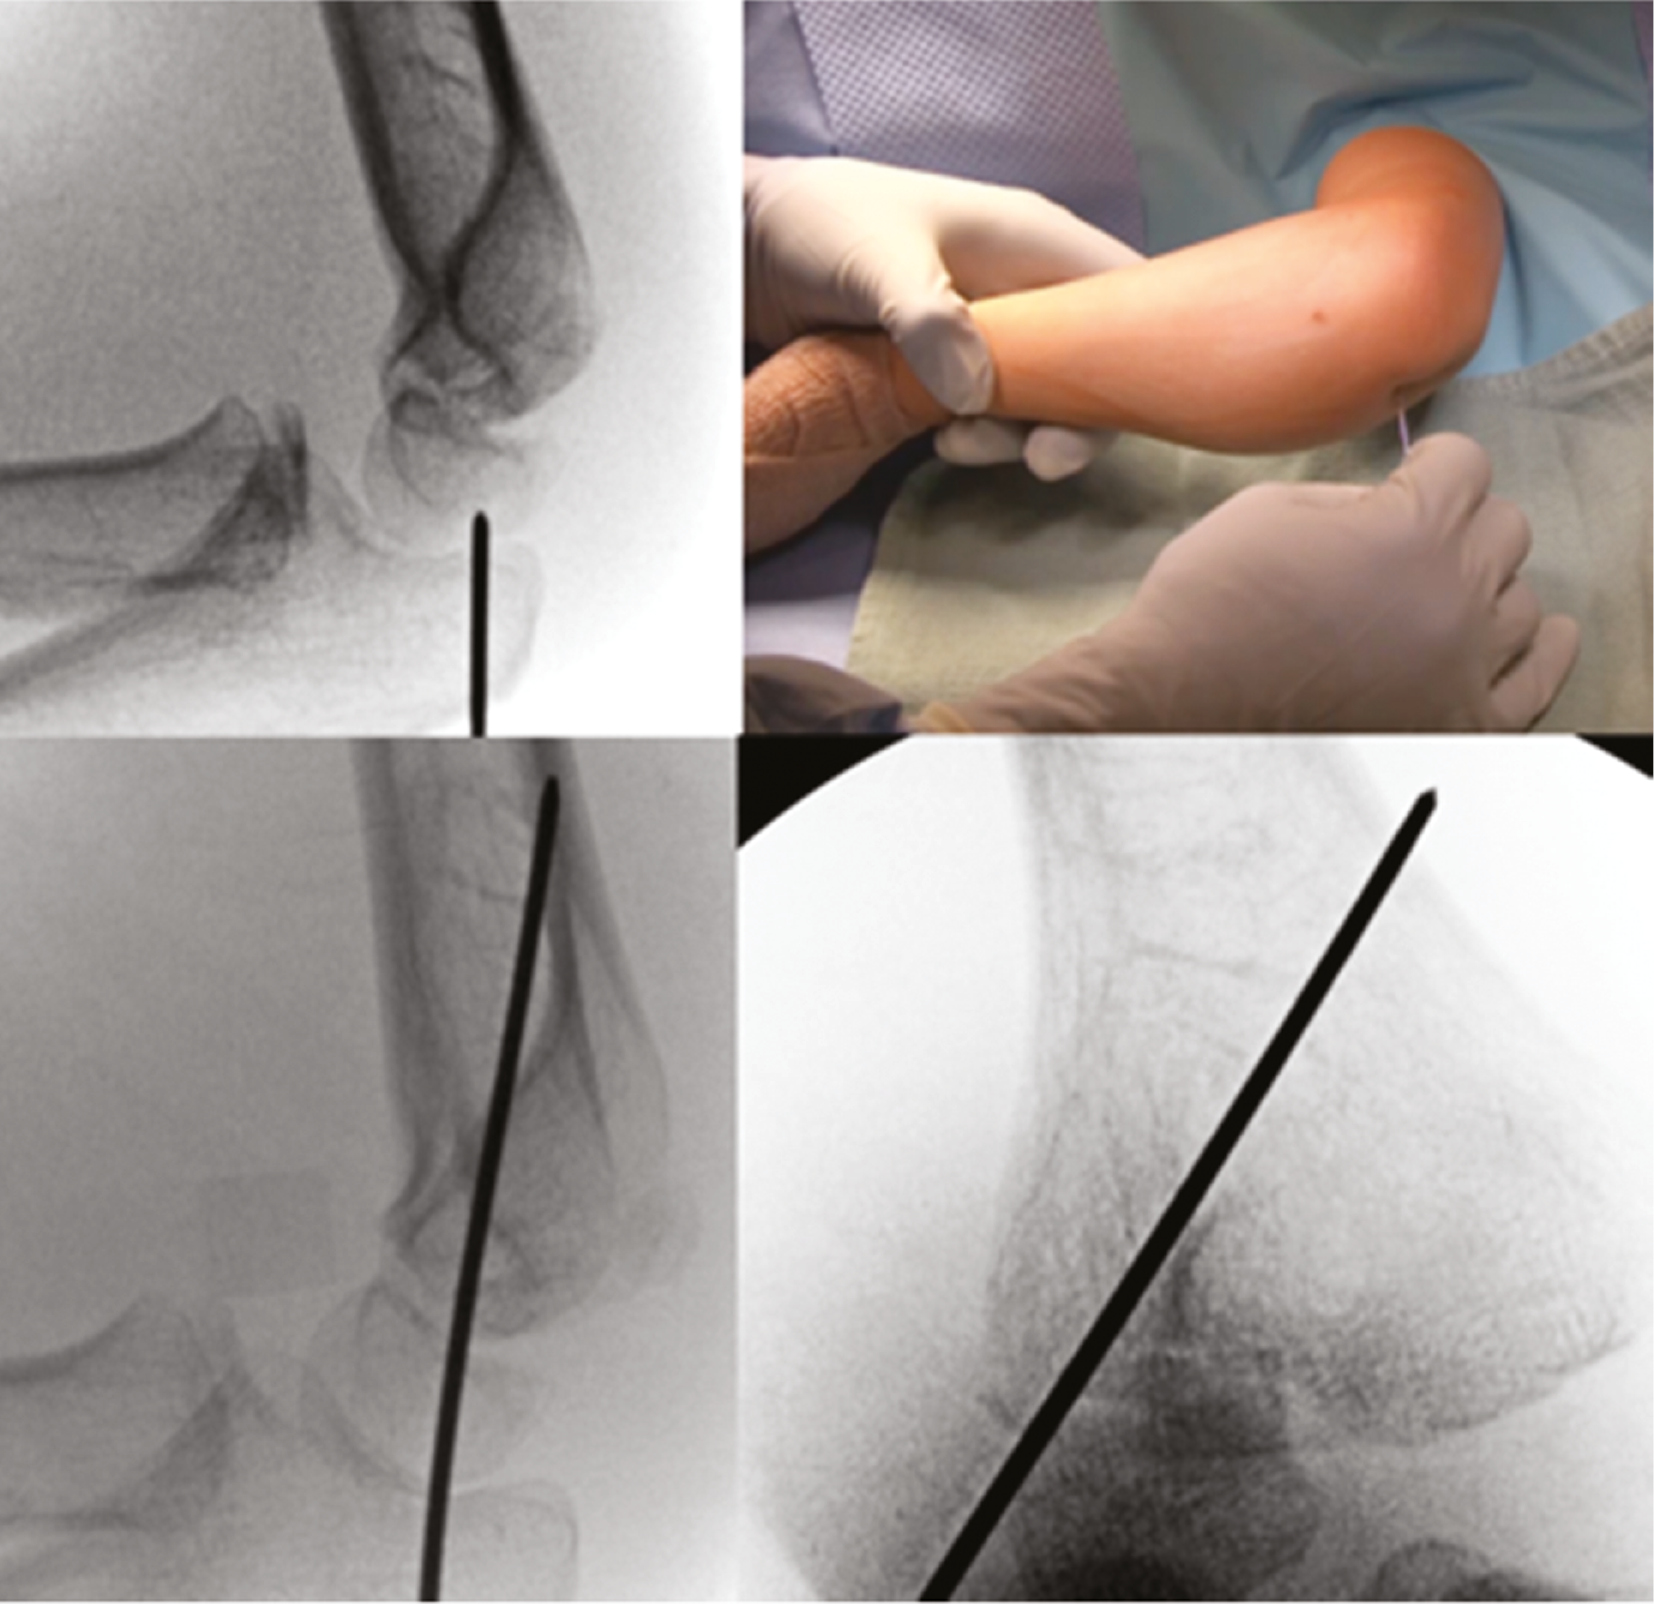

Operative Technique: The patient is prepped and draped with an extremity drape to expose up to the shoulder. An attempt at a closed reduction can be performed utilizing elbow varus and forearm pronation to disengage the fragments followed by supination and elbow valgus.4 Direct pressure with the surgeon’s thumb can improve the reduction (Figures 47).

Figure 4. A minimally displaced lateral fracture is partially reduced with thumb pressure.

jposna2023632_fig4.jpg

Figure 5. A single K-wire is used to provisionally fix lateral condyle fracture.

jposna2023632_fig5.jpg

Figure 6. Further compression can be obtained by using a cannulated depth gauge over the K-wire.

jposna2023632_fig6.jpg

Figure 7. A second wire is divergently placed to prevent displacement, and a third wire will be placed to finalize reduction.

jposna2023632_fig7.jpg